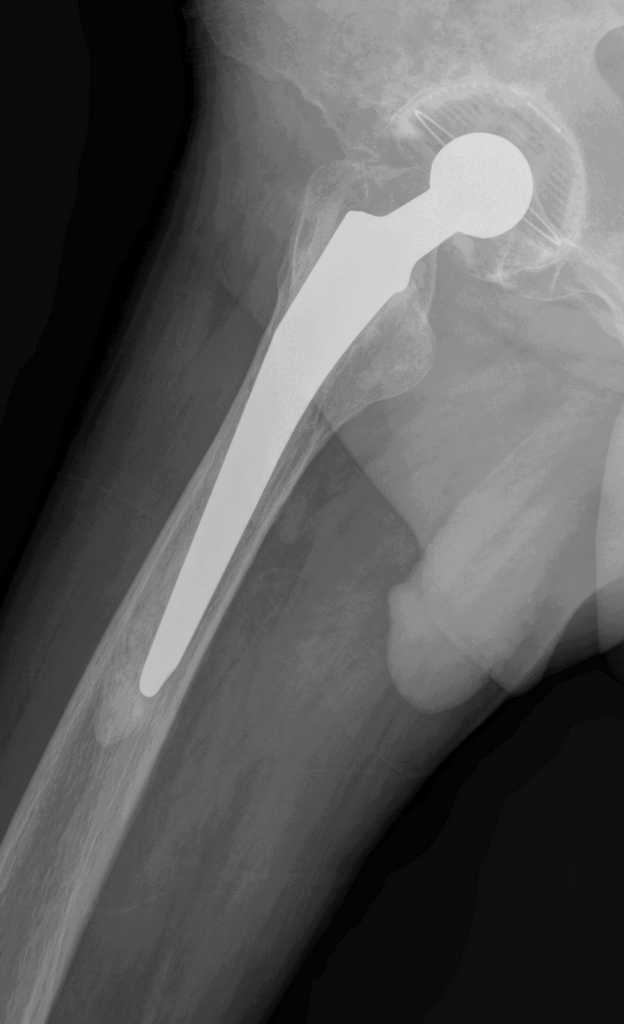

Уважаемые коллеги. Прошу оценить Р-граммы больного после протезирования т\б суставов.

Больной М.,75л. Страдает коксартрозом. В 2005 справа и в 2007 г. слева эндопротезирование т\б суставов.

Через полгода после операции появилась боль в правой паховой области, правом бедре(средней и верхней третях)при движениях и особенно осевой нагрузке на правую ногу.

На мой взгляд, оба бедренных компонента нестабильны, это и является причиной боли. Оба компонента явно меньше требуемого размера. Ножка Мюллера показывает отличные результаты, но только при формировании рассеченной цементной мантии.

Евгений, справа ножка нестабильна, возможно она уже развернулась в мантии, да и вокруг чашки есть просветления. Видимо надо планировать повторное вмешательство с удалением ножки и цемента. Ножка должна удалиться легко, цемент в значительной своей части тоже. Сменить ножку лучше на бесцементную и не обязательно ревизионную, пойдет любая с элементами диафизарной фиксации. Состояние впадины оцените во время операции.

Признаки нестабильности ножки заметные, выраженная демаркация зоны кость - цемент. Нестабильность чашки сомнительная. Согласен, не обязательно применение ревизионной ножки, но фиксацию предпочел бы цементную. Данный метод фиксации уменьшает риск интраоперационного перелома бедра, упрощает и ускоряет период реабилитации пациентов пожилого возраста. Вероятно, желательно применить другой тип ножки, я бы использовал CS (CSL) -PLUS Plus Orthopedics, т.с."бюджетный" вариант. Может возникнуть проблема с удалением цементной "пробки".

Уважаемый Евгений, понятие стресс шилдинга не является синонимом нестабильности, хотя и является признаком неадекватности распределения нагрузки в системе "имплантат - кость" и может в последствие привести к "расшатыванию" эндопротеза.В данном случае на рентгенограмме правого тазобедренного сустава отчетливо видна сформированная "замыкательная пластинка" на внутреней поверхности кости (на границе с цементом). Причем, как раз в проксимальном отделе сегмента, то есть в зоне определяющей стабильность имплантатов типа Мюллер.

Болевой синдром в тазобедренном суставе при осевой нагрузке не характерен для корешкового с-ма или ишалгии. В данном случае, скорее всего мы наблюдаем "обратный" "с-м поршня". Когда изменение давления в костномозговом канале за счет перемещения нестабильной ножки (поршня)передается не в дистальные отделы бедра (классический "с-м поршня"), а за счет неподвижной (или малоподвижной) цементной пробки "отражается" в проксимальную часть, где и возникает боль. Возможно, конечно и наложение неврологическои и ортопедической симптоматики. Но, на мой взгляд, данные рентгенограммы дают достаточно информации о наличие проблем, по крайней мере, со стороны ножки эндопротеза правого тазобедренного сустава. А R-граммы, действительно хорошие... по качеству.

На мой взгляд имеет место нестабильность обоих бедренных компонентов. Боль, которая имеет место у больного характерна при проблемах в области тазобедренного сустава. Нужно рассматривать вопрос о ревизионном эндопротезировании, в частности бедренного компонента.